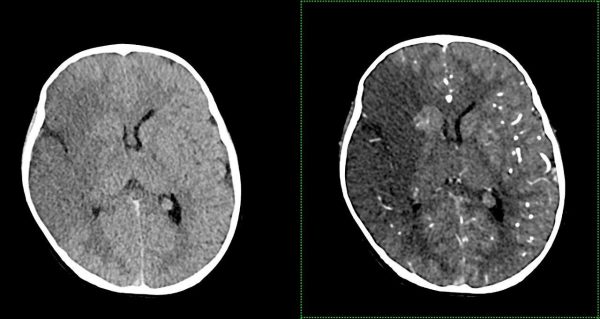

- КТ: створює детальні зображення кісток та м’яких тканин у вигляді “зрізів”. Дозволяє виявити навіть найменші зміни.

Комп’ютерна томографія: Надає детальні зображення внутрішніх органів та тканин, допомагає виявити пухлини, запалення та травми.

Магнітно-резонансна томографія: Найточніший метод для дослідження мозку, хребта, суглобів та м’яких тканин. Абсолютно безпечний тому також підходить для візуалізації вагітних, дослідженні плоду. Разом КТ та МРТ показані для виявлення вроджених аномалій розвитку/патології центральної нервової, скелетно-м’язової, травної, дихальної, сечовидільної системи, статевої сфери Також показані пацієнтам та потенційним донорам при підготовці до трансплантації,

- Комп’ютерна томографія: Siemens SOMATOM X.cite (128 зрізів, мах. 364 реконструйовані зрізи)